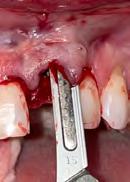

3. Image 3a: Tooth #9 was extracted with minimal flap elevation, preserving the papillae. Image 3b: A 3.6 x 15 mm implant was placed in a fully guided manner with a palatal bias to maximize the facial gap dimension, achieving a +2mm gap.

4. Image 4a: The underside of the periosteum was incised just apical to the mucogingival junction, and a supra-periosteal pocket was created using sharp dissection with a #15 blade. Image 4b: The facial gap was packed with 50 mg of Geistlich Bio-Oss Collagen®. A cover screw was temporarily placed to prevent bone graft granules from entering the implant chamber.